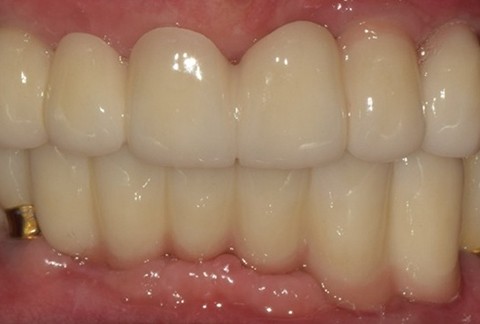

임플란트-보철-시-기성-어버트먼트가-아닌-맞춤-지대주-사용-보철-파절-위험-방지-음식물-끼임-방지-주위염-방지-맞춤-지대주는-환자의-구강환경에-맞는-교합을-구현할-수-있고-앞니-보철시-더욱-심미적으로-제작이-가능합니다

임플란트-전후사진